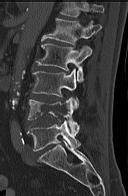

Figures 1 through 3 show sagittal and axial MRIs and a radiograph from a

77-year-old woman with leg pain when standing and walking of 1 year duration. The pain improves when she leans forward. She has been in physical therapy, taken oral analgesics, and had epidural injections with minimal relief. What is the best next step?

4. Microdiskectomy Discussion: B

The patient has lumbar stenosis of L2-3 and L3-4. She has no spondylolisthesis or instability. For her condition, spinal fusion plays a minimal role. She has no evidence of instability, and her condition can be addressed through laminectomy only. No role exists for microdiskectomy, because her disease results from a combination of ligamentum flavum hypertrophy and facet hypertrophy.